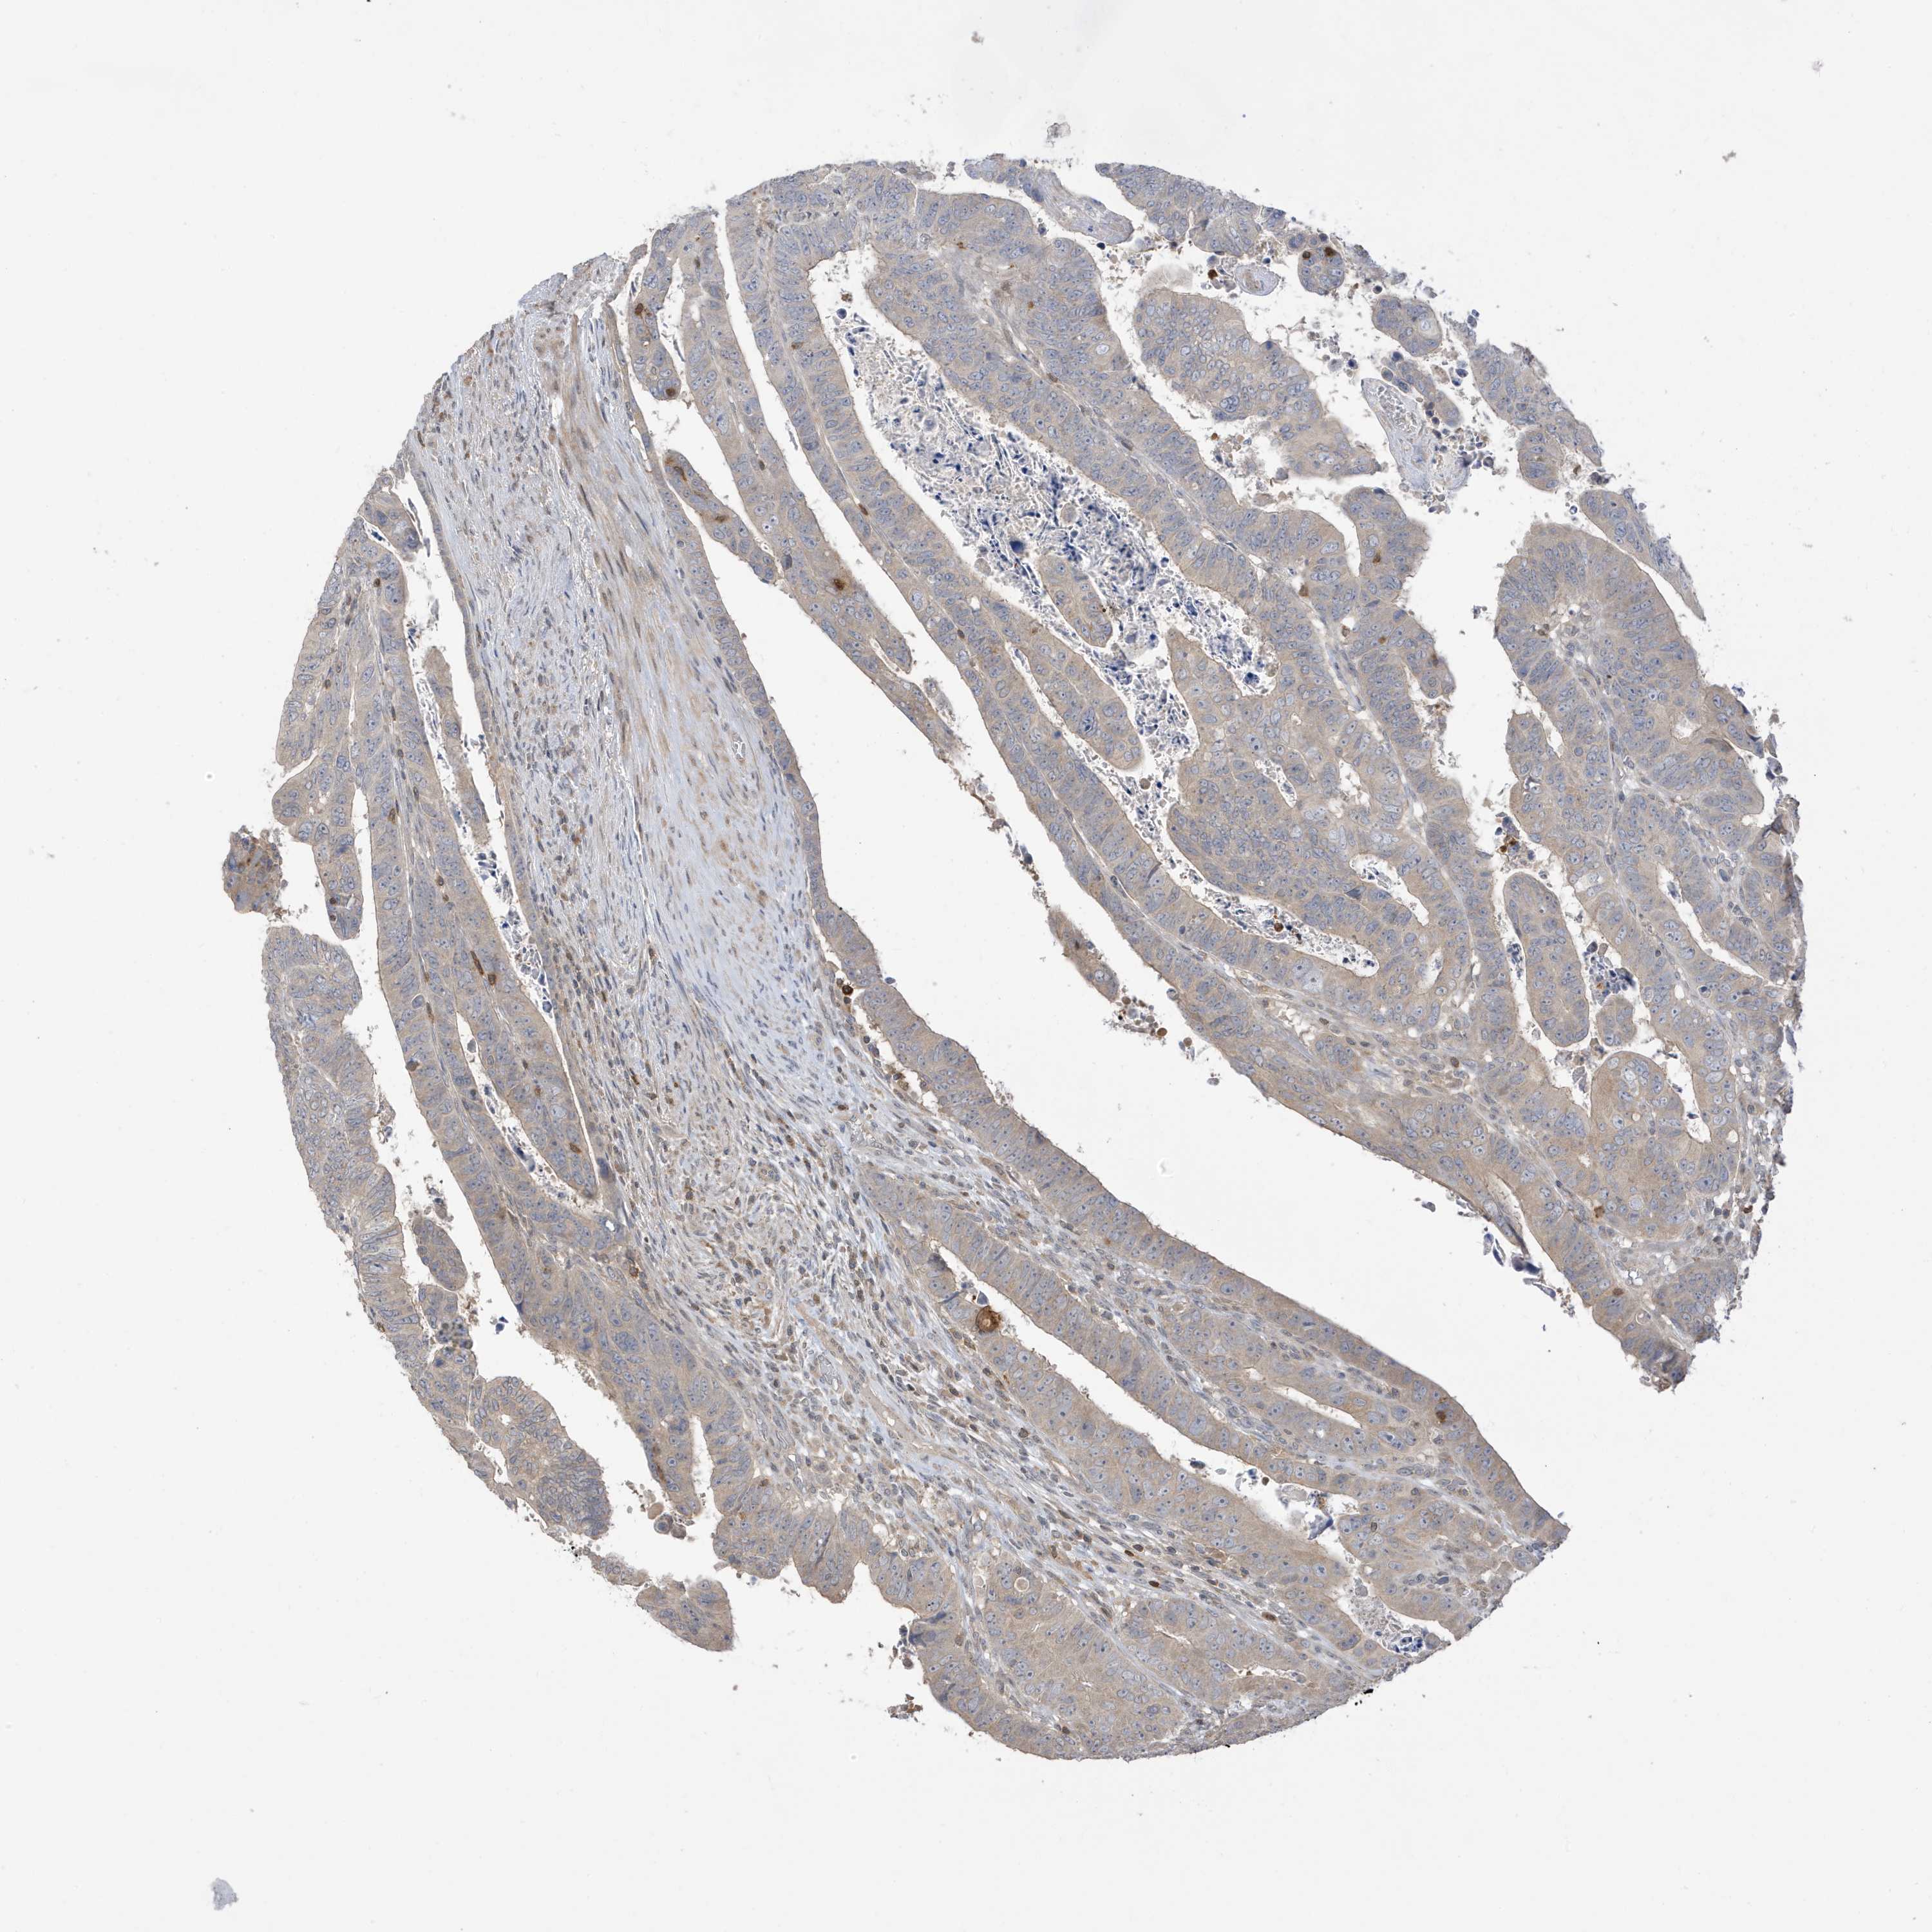

CANCER COLORECTAL CANCER Show tissue menu

Colorectal cancer

Human cancer

Colon adenocarcinoma